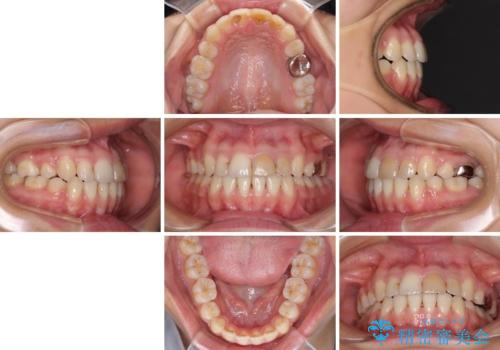

八重歯の抜歯矯正 費用を抑えた矯正装置

- 20代女性

- 矯正装置

- メタルブラケット

- 上の八重歯を気にして来院された患者様です。

受け口傾向にあるため、上顎前歯の叢生解消とともに下顎前歯を後方へ移動させることを目的とし、上下左右の第一小臼歯4歯を抜歯することとしました。

受け口傾向の方の下顎抜歯矯正では、下顎前歯の歯肉が退縮することがあります。前歯を移動させるときには、歯肉退縮が起こらないように工夫する必要があります。